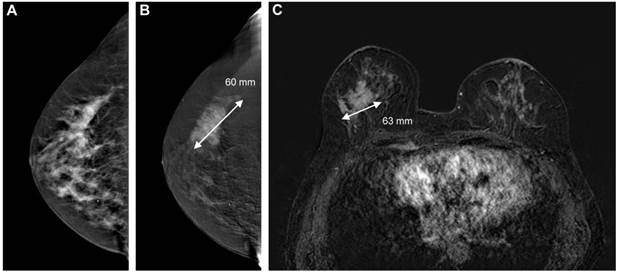

In Figure 4 and 5, examples of good and poor agreement between tumor diameter measurement between CESM and breast MRI can be appreciated.

Figure 4

Image example of good agreement between tumor diameter measurements using CESM and breast MRI. The cancer is ill-defined on the low-energy CESM image (A) and can be measured more confidently on the recombined image (B, 60 mm). Subtracted contrast-enhanced T1w images (C) showed a similar irregular mass (63 mm). Final pathological results showed a 60 mm invasive ductal carcinoma.